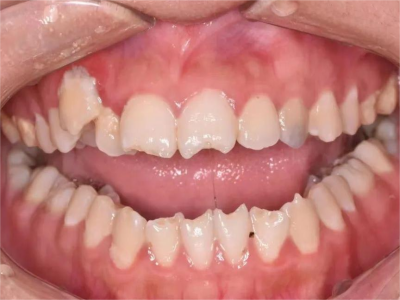

先天性梅毒牙主要表现为半月形切牙以及桑葚状磨牙,具体表现如下:

1、半月形切牙:上中切牙及下中切牙切缘较牙冠中部窄,中央部有切迹,两切角圆钝,有如新月形,因牙齿形态变化,使牙间空隙增大。